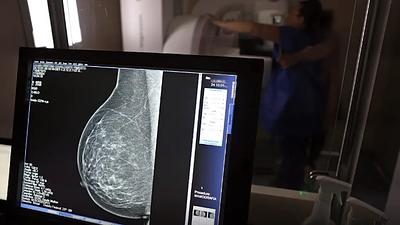

Escassez de mamógrafos dificulta prevenção do câncer de mama

O Brasil tem uma cobertura muito baixa de mamografias: 24%. O ideal recomendado pela Organização Mundial da Saúde é de 70%.